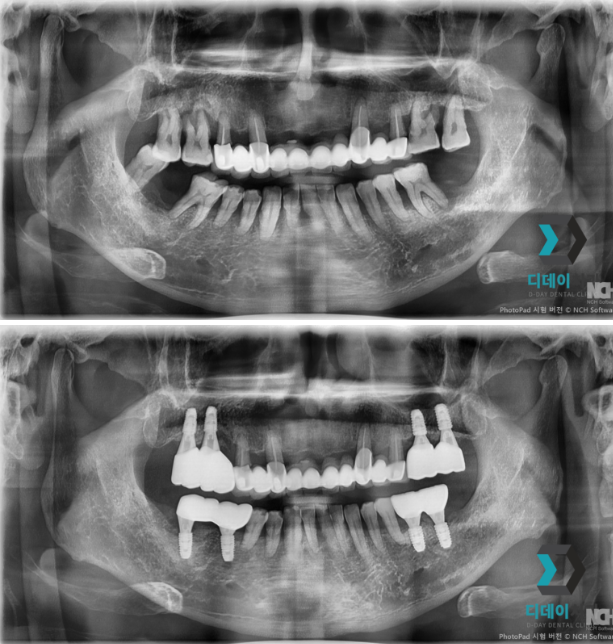

양쪽 위아래 어금니 치주염으로 내원하신 환자분입니다.

양쪽 어금니 심한 치주염으로 인해 발치 후

즉시 임플란트 식립 진행했습니다

양쪽 위아래 어금니 치주염으로 발치 후 즉시 임플란트 식립

25-07-15